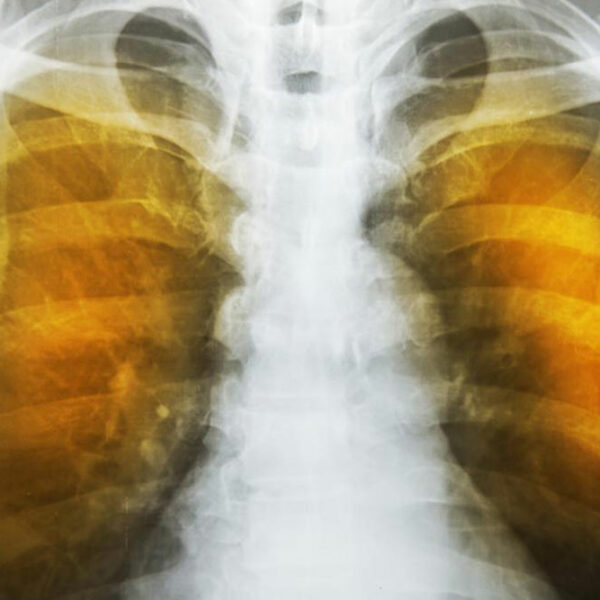

Emphysema is an oppressive respiratory disorder which results from the disintegration of the alveoli, i.e., the tissues where the interchange of gas with blood takes place. Destruction in any large scale will reduce the gas transfer area and the process of gas transfer itself, leading to oxygen starvation or hypoxia. When conventional treatment with bronchodilators, corticosteroids etc. have ceased to give relief, one has to resort to a method known as Long Term Oxygen Therapy or LTOT.

Another complication is the alveoli becoming weaker, and then starting to break. When this assumes larger scale, vacant spaces are formed called bullae. This reduces the gas transfer area as well as the capacity of the lung to expand. These are often have to be surgically removed to allow more space for the lung to expand. In the ultimate case, lung transplant becomes the only choice. Another scenario is a large-scale disintegration of alveoli that can cause pneumothorax, which is a condition in which the chest cavity is filled with air and the lungs collapse. This is a very serious condition if not fatal.